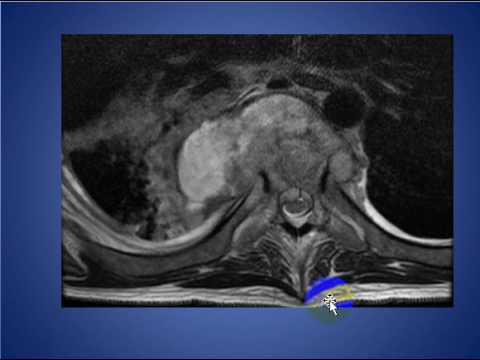

Middle and Posterior Mediastinal Masses for Radiology Board Review